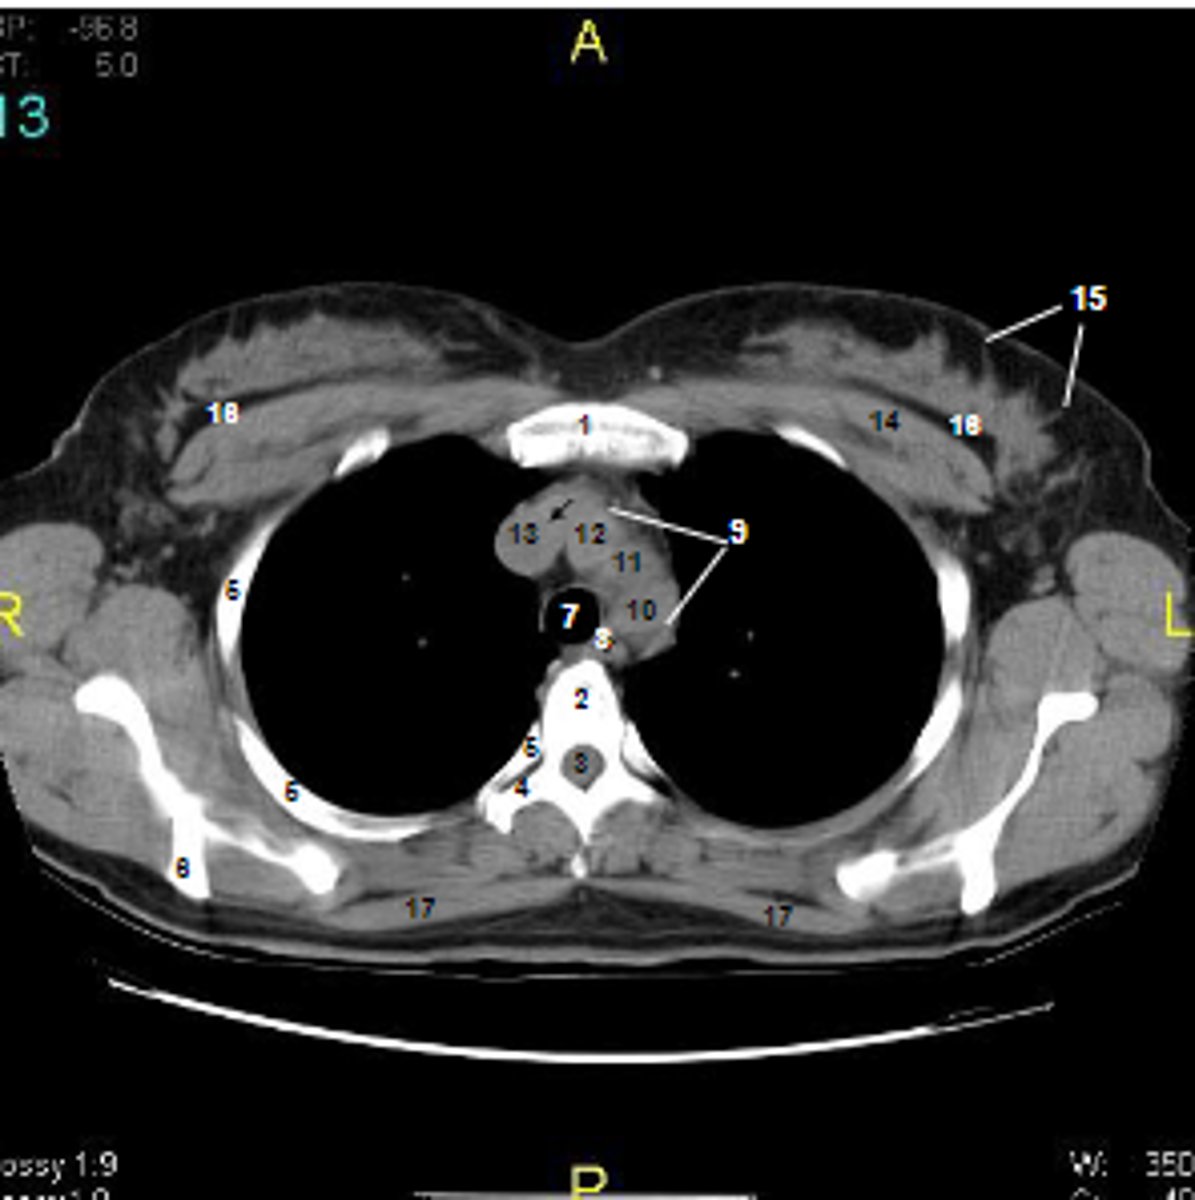

1

at what number is the sternum

2

at what number is the vertebral body

3

at what number is the vertebral canal/ spinal cord

4

at what number is the transverse process of vertebra

5

at what number is the rib

6

at what number is the spine of scapula

7

at what number is the trachea

8

at what number is the esophagus

9

at what number is the arch of aorta

10

at what number is the left subclavian artery

11

at what number is the common carotid artery

12

at what number is the brachiocephalic trunk

13

at what number is the superior vena cava

14

at what number is pectoralis major

15

at what number are Cooper's ligaments

16

at what number is the retromammary space

17

at what number is trapezius